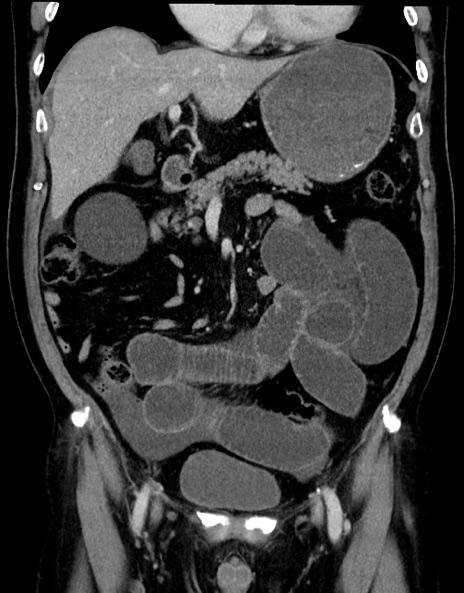

症例15(冠状断像)

【症例】70歳代男性

【主訴】腹痛

【現病歴】今朝から腹痛あり。全体的に痛い。特に左上の方。排ガスが今日はない。冷や汗が出る。

【既往歴】直腸癌術後

【身体所見】左側腹部〜上腹部に圧痛あり。腹膜刺激症状明らかなではない。軽度反跳痛。左下腹部に術後瘢痕あり。

【データ】WBC 7700、CRP 0.02